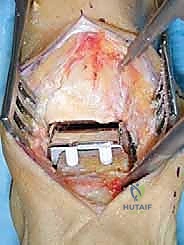

1. مكون عظم الساق (الظنبوب - Tibial Component)

يُصنع هذا المكون من سبيكة معدنية فائقة القوة من الكوبالت والكروم (Cobalt-Chromium Alloy).

* التصميم: يتكون من لوحة تحميل مسطحة بسُمك 4 مم فقط. هذا السُمك الرقيق مقصود جداً؛ فهو يقلل من الحاجة إلى إزالة كميات كبيرة من العظم الطبيعي للمريض (عادة يتم إزالة 2 إلى 3 مم فقط من العظم تحت القشري). الحفاظ على العظم هو مبدأ أساسي في جراحات العظام الحديثة.

* التثبيت البيولوجي: السطح العلوي الملامس للعظم يحتوي على نتوءات هرمية دقيقة لزيادة الثبات الأولي. الأهم من ذلك، أنه مغطى بطلاء مسامي من التيتانيوم وهيدروكسي أباتيت (Hydroxyapatite). هذا الطلاء يحفز العظم الطبيعي على النمو والاندماج داخل المسامات المعدنية، مما يوفر تثبيتاً بيولوجياً دائماً ومستقراً مدى الحياة دون الحاجة إلى أسمنت عظمي.

* الدرع الأمامي: يتميز بوجود شفة (درع) أمامية يمكن تثبيتها بمسامير دقيقة لضمان عدم تحرك المكون من مكانه تحت تأثير القوى القاصة.

2. مكون عظم الكاحل (القدم - Talar Component)

يُصنع أيضاً من سبيكة الكوبالت والكروم.

* التصميم التشريحي: يتميز بشكل مخروطي فريد، حيث يكون نصف القطر أصغر من الناحية الإنسية (الداخلية) مقارنة بالناحية الوحشية (الخارجية). هذا التصميم ليس عشوائياً، بل هو نسخة مطابقة لتشريح عظم الكاحل الطبيعي، مما يسمح بحركة دورانية طبيعية أثناء المشي.

* الأسطح المفصلية: السطح الخارجي مصقول بدرجة عالية جداً (كالمرايا) لضمان انزلاق سلس وتقليل تآكل المكون البلاستيكي إلى أدنى حد ممكن.

* الأجنحة الجانبية: يحتوي على جناحين مصممين تشريحياً يغطيان الأسطح الجانبية لعظم الكاحل، مما يوفر دعماً إضافياً ويحاكي الأسطح الغضروفية الأصلية بدقة.

3. المكون المتحرك (البولي إيثيلين عالي الوزن الجزيئي - UHMWPE)

هذا هو "الغضروف الصناعي" والسر وراء نجاح مفصل HINTEGRA.

* المادة: مصنوع من بلاستيك طبي متطور جداً يتحمل الضغط الشديد والاحتكاك المستمر.

* حرية الحركة: على عكس المفاصل القديمة حيث يكون البلاستيك مثبتاً في المعدن (Fixed Bearing)، في مفصل HINTEGRA، يكون هذا المكون حراً ومتحركاً (Mobile Bearing). سطحه العلوي مسطح لينزلق بحرية فوق مكون الساق، وسطحه السفلي مقعر ليتطابق مع مكون الكاحل.

* الفوائد البيوميكانيكية: هذا التصميم الحر يسمح للمفصل بالدوران المحوري، الانثناء، والتمدد بشكل يحاكي الكاحل الطبيعي بنسبة مذهلة. كما أنه يقلل من إجهاد القص (Shear Stress) على واجهة العظم والمعدن، مما يقلل بشكل كبير من خطر ارتخاء المفصل على المدى الطويل. يتوفر بسماكات متعددة (5، 6، 7، 9 مم) لضبط التوازن الدقيق لأربطة المريض أثناء الجراحة.